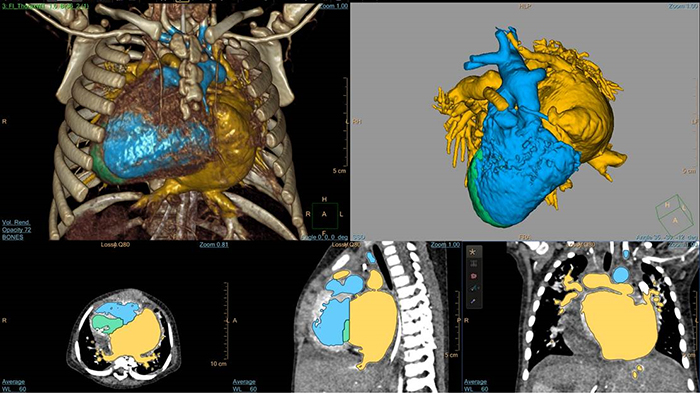

5-day old D-TGA analysis with HeartNavigator

3D modeling with IntelliSpace Portal

EchoNavigator heart model segmentation